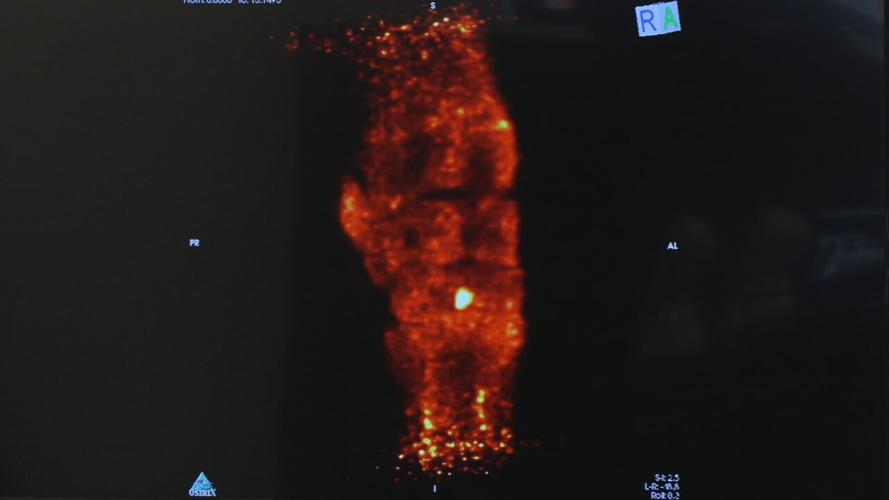

A positron emission tomography (PET) scan machine works in about five minutes. It can help veterinarians find any problems with a racehorse's legs to prevent injuries.